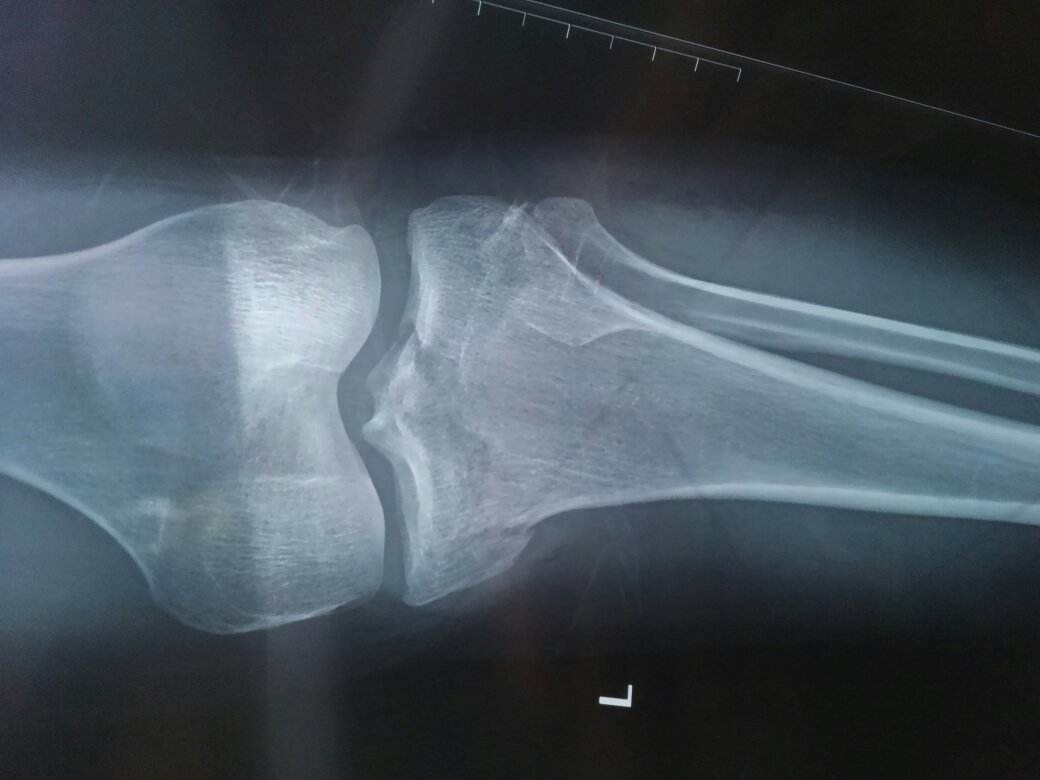

脛骨結(jié)節(jié)骨軟骨病一般指脛骨結(jié)節(jié)骨骺炎,脛骨結(jié)節(jié)骨軟骨炎,脛骨結(jié)節(jié)骨骺無菌性壞死。從多種病因?qū)W的命名來看,對其發(fā)病原因,病理實(shí)質(zhì)認(rèn)識不統(tǒng)一,國外文獻(xiàn)多稱Osgood-Schlatter病,是1903年由Osgood和Schlatter分別同期報告。